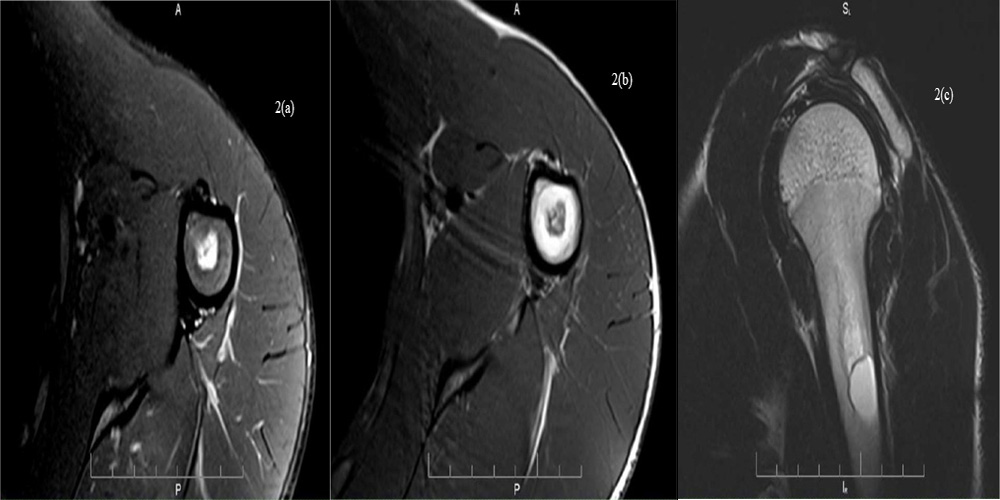

• MR images of the left humerus show central mass without interruption of the cortex. On T1 it shows central zone of in - termediate signal with peripheral hyperintensity, on T2 the central zone shows mixed high and low signal with peripheral hyperintensity and PD fat suppression sequences the periph - eral area shows total signal cancellation. (Figure 1 and 2).

The MRI findings indicated the presence of hemorrhage in the intraosseous fatty tumor.

Figures 2 (a-c): MR images of the left humerus shows central mass with - out interruption of the cortex. On axial T1 it shows central zone of inter - mediate signal with peripheral hyperintensity, on sagittal T2 the central zone shows mixed high and low signal with peripheral hyperintensity and on axial PD fat suppression sequences the peripheral area shows total signal cancellation.